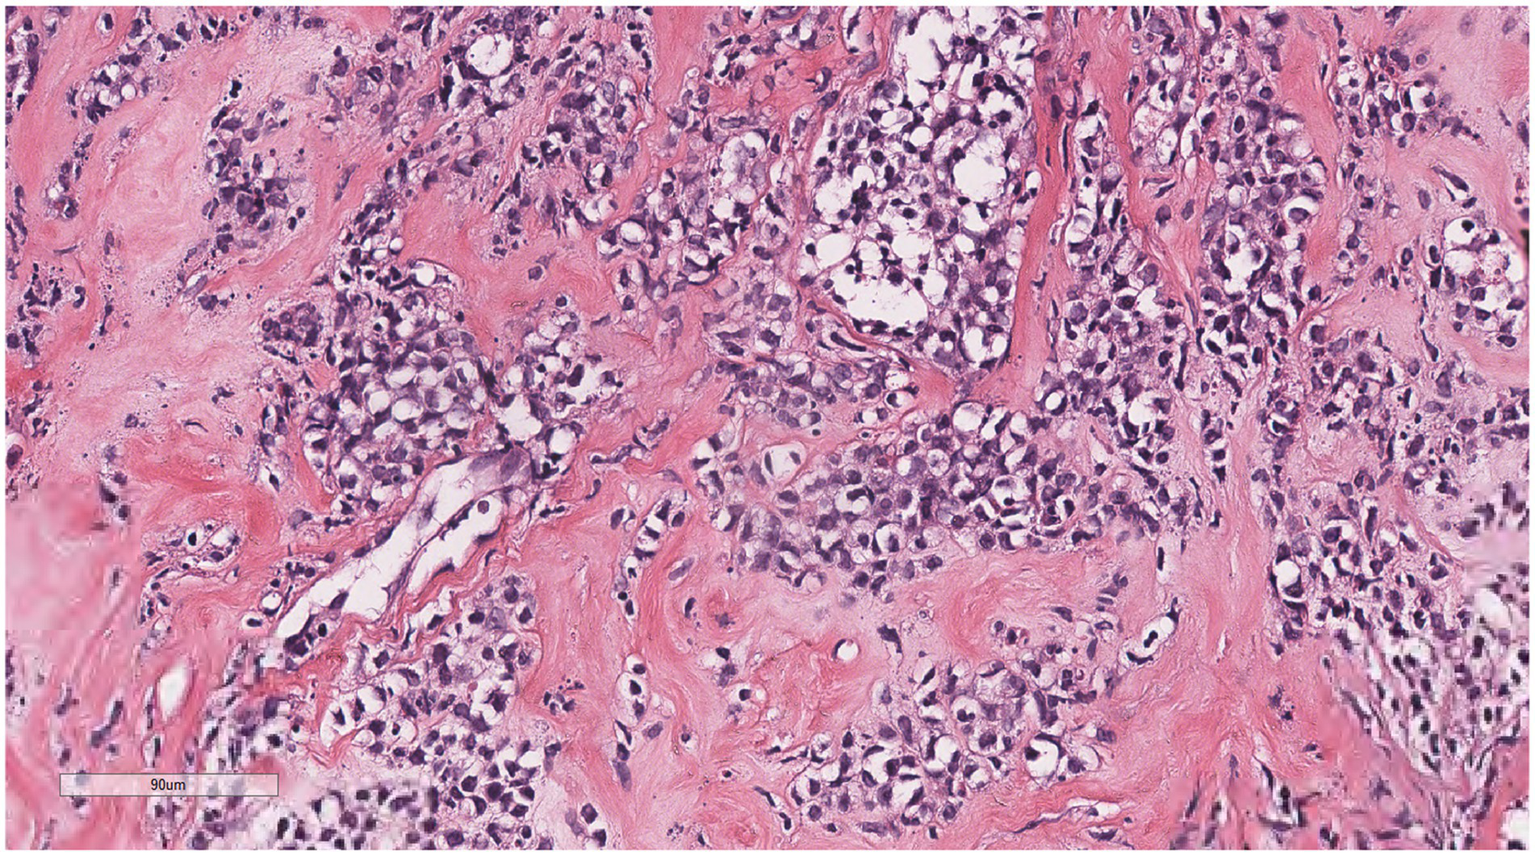

Microscopically (Figures 2–8), the breast biopsy tissue revealed diffuse proliferation of lymphocyte-like cells arranged in cords or nests, which infiltrated the breast stroma and surrounding fat. At medium magnification, patches of mononuclear cells with loose arrangements and uniform dispersion were observed. Some of these cells were arranged in a linear or nonpiled pattern, with slender fibrous septa visible. The cells were medium to large, with indistinct nucleoli, primitive to folded nuclei, fine chromatin, scattered eosinophils, and mitotic figures. Some of the cells were medulloblastoid, with scant cytoplasm, round nuclei, and small nucleoli. Some of the cells were myelomonocytic or monocytoid, with local fibrous tissue proliferation.

Figure 2

Biopsy tissue of the breast at low magnification, showing no obvious lobular structure of the breast.

Figure 3

At low magnification, the tumor appears as a cord-like distribution.

Figure 4

At medium magnification, the tumor cells were arranged in cords or nests and grew infiltratively into the breast stroma.